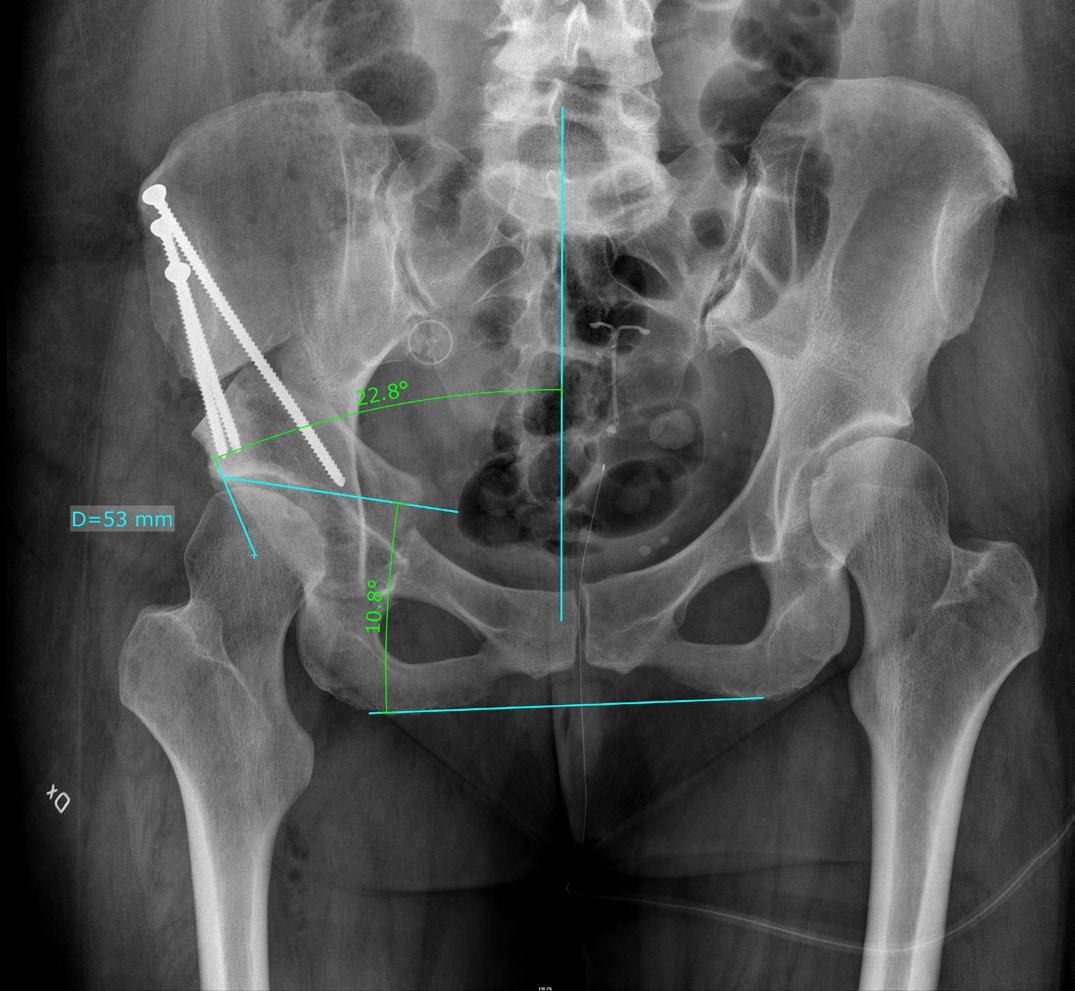

PostPEVA omfattar olika problemtyper; underkorrektion, överkorrektion, talusdeformitet, navicularedeformitet och bal ansering av foten. Under korrierade fötter innefattar kombinationer av spetsfot, varus, cavus, adduktus och framfotssupination medan en överkorrigerad fot in nebär olika grader av valgus fot eller gungfot. Plattfothet eller valgusfot vid postPEVA kan dock inte hanteras som en ”vanlig” plattfothet.

PostPEVA är en stor utmaning för kirurgen! För att kunna hjäl pa patienterna optimalt måste man förstå i) heterogeniteten och komplexiteten i deformiteterna ii) koppling mellan stelhet, fotdeformitet och röntgenförändringar och iii) vad som är or saken till upplevd smärta och funktionsnedsättning.

”PostPEVA” omfattar vuxna PEVA-behandlade patienter (> 16 år) med besvär från sin behandlade fot med kvarstående defor mitet eller en överkorrektion.